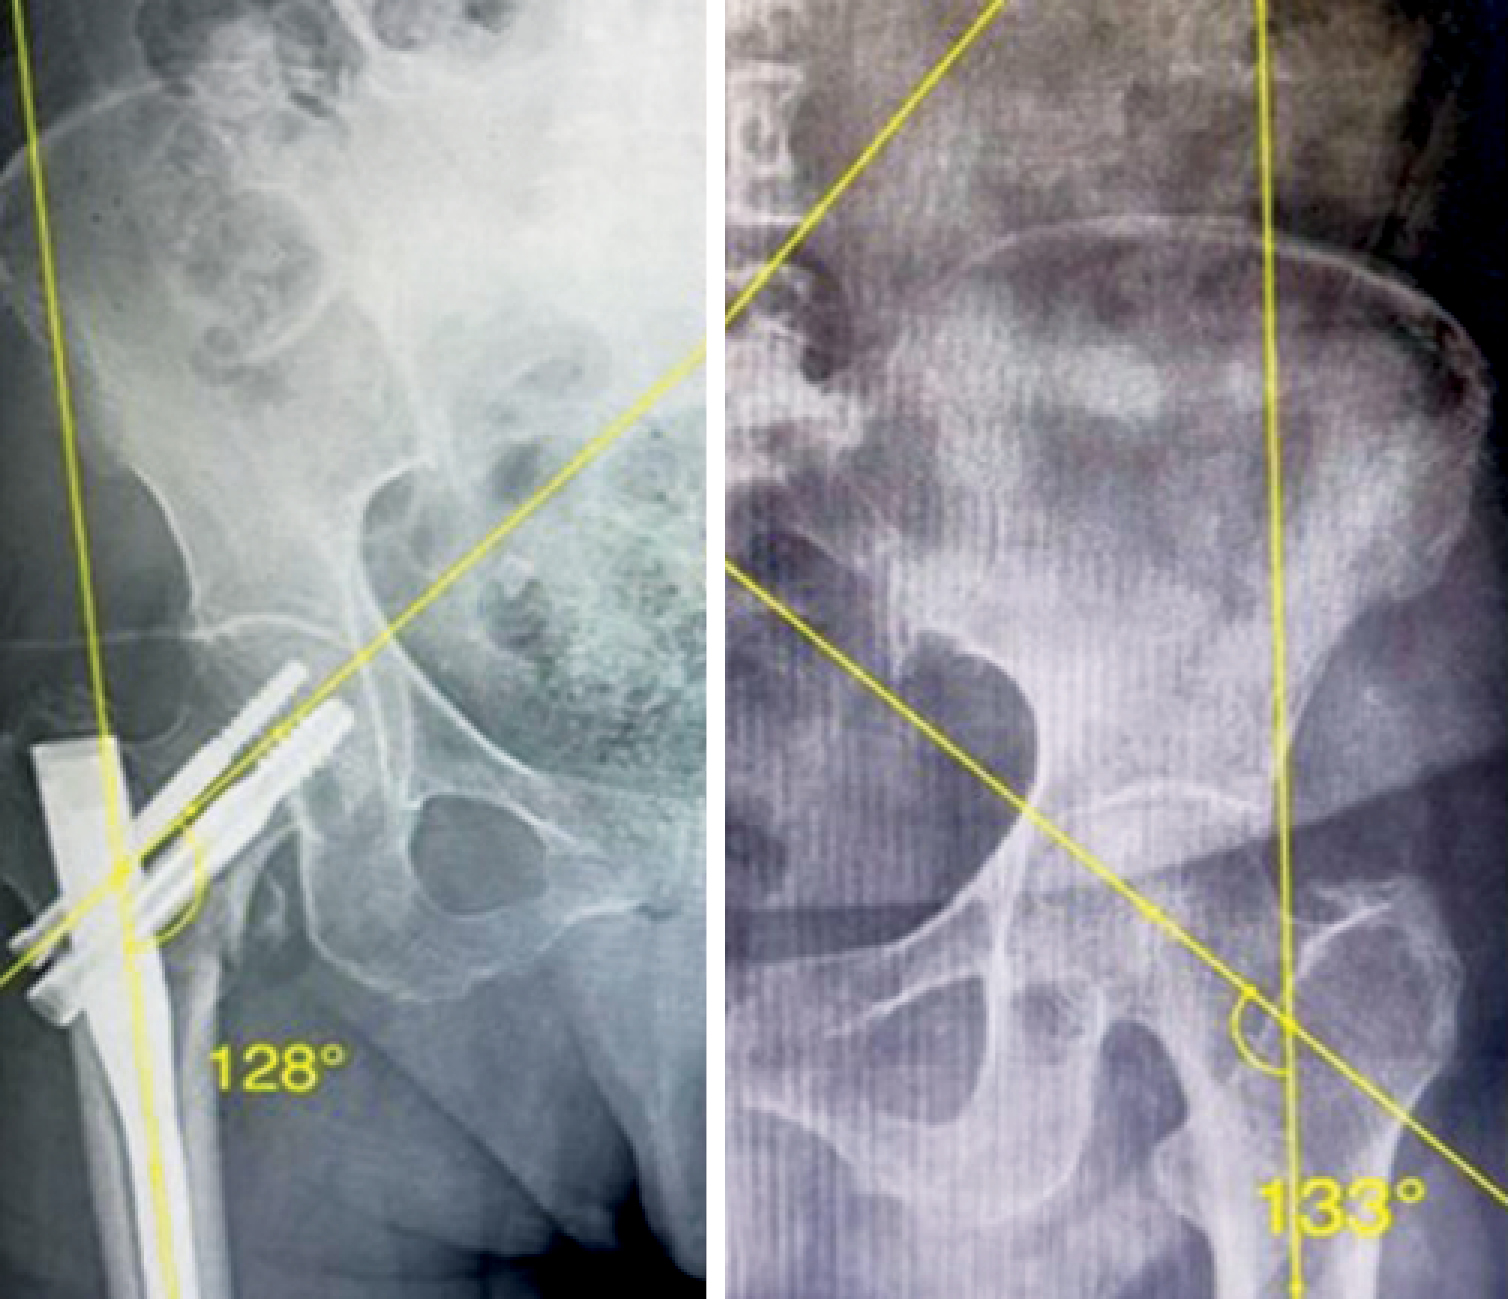

Postoperative evaluation included immediate anteroposterior (AP) and lateral X-rays of the hip. The femoral NSA was determined according to the methodology described by C. K. Boese et al. [10]. This angle was calculated between the axis of the femoral neck and the anatomical axis of the FS. The neck axis was drawn from the femoral head center (HC) to the neck center (NC), the latter defined as the midpoint between points where a circle (centered on the HC) intersected the superior and inferior borders of the femoral neck. The shaft axis was established by connecting central points identified at both proximal and distal segments of the femoral diaphysis [11]. The tip-apex distance (TAD) was calculated as the cumulative length from the screw tip to the apex of the femoral head as seen on both the AP and lateral projections [12]. FS lateralization was assessed by measuring the horizontal distance from the femoral head center to a reference line parallel to the lateral cortex of the femur, comparing the injured side with the contralateral uninjured side [7] (Figures 1, 2).

Figure 2. Calculation of the wedge effect (net lateralization of the shaft compared to the head/neck segment): line B represents the distance from the center of the femoral head (C) to the lateral femoral shaft (A)

Figure 3. X-ray of a patient from the DHS group: a — postoperative neck-shaft angle; b — neck-shaft angle of contralateral unaffected side

Figure 4. X-ray of a patient from the PFN group, showing 5 degrees of varus malalignment as compared to the unaffected contralateral side

In the PFN group (n = 20), the mean lateralization of the FS on the injured side was statistically significantly higher compared to the DHS group (56.60±7.07 vs 49.50±6.59 mm; p = 0.002). However, on the non-injured side, there was no statistically significant difference between the PFN group and the DHS group (51.65±4. vs 49.65±6.09 mm; p-value = 0. 261) (Figures 5, 6, 7).

Figure 6. X-ray of a patient from the DHS group, showing femoral shaft lateralization (uninjured side — 50 mm, injured side — 49 mm)

Figure 7. X-ray of a patient from the PFN group, showing femoral shaft lateralization (uninjured side — 47 mm, injured side — 54 mm)